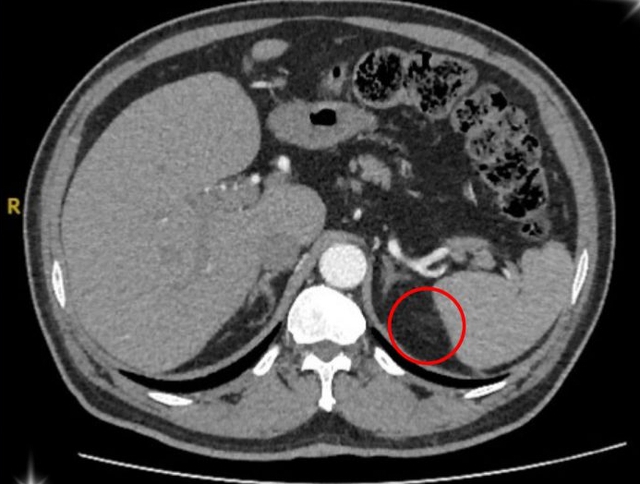

Hình ảnh vùng ổ bụng của bệnh nhân u tuyến thượng thận. Ảnh: BVCC

Sau quá trình kiểm tra kỹ lưỡng, ông T. được xác định mắc phải hội chứng Conn (hay còn gọi là cường Aldosterone tiên phát) – một bệnh lý hiếm gặp do khối u nhỏ ở vỏ tuyến thượng thận gây ra.

Theo BS. Đinh Công Thịnh – Bác sĩ Khoa Ngoại Tiết Niệu, tuyến thượng thận là cơ quan nội tiết nhỏ nằm phía trên thận, đóng vai trò quan trọng trong việc sản xuất hormone giúp điều hòa huyết áp, cân bằng nước, điện giải và kiểm soát quá trình chuyển hóa của cơ thể.

Khi xuất hiện khối u, tuyến này tăng cường tiết ra aldosteron (là hormone giúp điều hòa natri và kali trong máu). Khi lượng hormone này tăng quá mức, người bệnh sẽ rơi vào tình trạng tăng huyết áp kéo dài, hạ kali máu, mệt mỏi, đau đầu, chuột rút, thậm chí rối loạn nhịp tim.